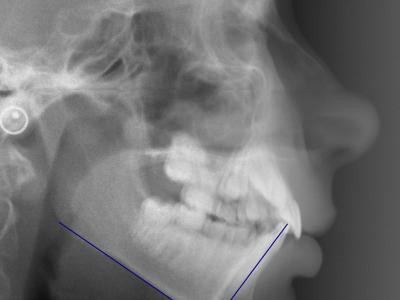

Vues endo-buccales (a, b, c) et téléradiographie de profil initiales avec IMPA=105° (d);

vue endo-buccales (e, f, g) et téléradiographie de profil (h) à 1 an post-opératoire (sans traitement orthodontique) montrant un redressement spontané des incisives mandibulaires avec IMPA=94° et une avancée du point B ;

superposition avec le logiciel Procuste (Rouge = Avant / Bleu = Après) montrant le repositionnement incisif et la croissance mandibulaire (i) ;

vue endo-buccales (j, k, l) et téléradiographie de profil (m) à 4 ans post-opératoires, avec traitement orthodontique multi-attaches et 1 an de contention, l’IMPA est resté stable à 94°.

Téléradiographie de profil initiale, IMPA = 108° (a),

à 11 mois post-opératoires avec 8 mois de nivellement sur arc rond, les incisives mandibulaires se redressent spontanément de 11° (IMPA = 97°) et la concavité de la symphyse diminue significativement (b),

superposition avec le logiciel Procuste (Rouge = Avant / Bleu = Après) (c).

Téléradiographie de profil avant traitement (a),

téléradiographie de profil de réévaluation à 12 mois de traitement multi-attaches montrant l’aggravation de la proalvéolie mandibulaire avec IMPA=110° (b), l’affaiblissement labio-mentonnier est décidé à ce moment,

téléradiographie de profil en fin de traitement après 9 mois de finitions sur multi-attaches et 1 an de contention, l’IMPA est réduit à 100° et le muscle mentonnier s’est relâché (c),

superposition avec le logiciel Procuste (Rouge = Avant / Bleu = Après) montrant le redressement radiculaire des incisives mandibulaires et la croissance mandibulaire (d)